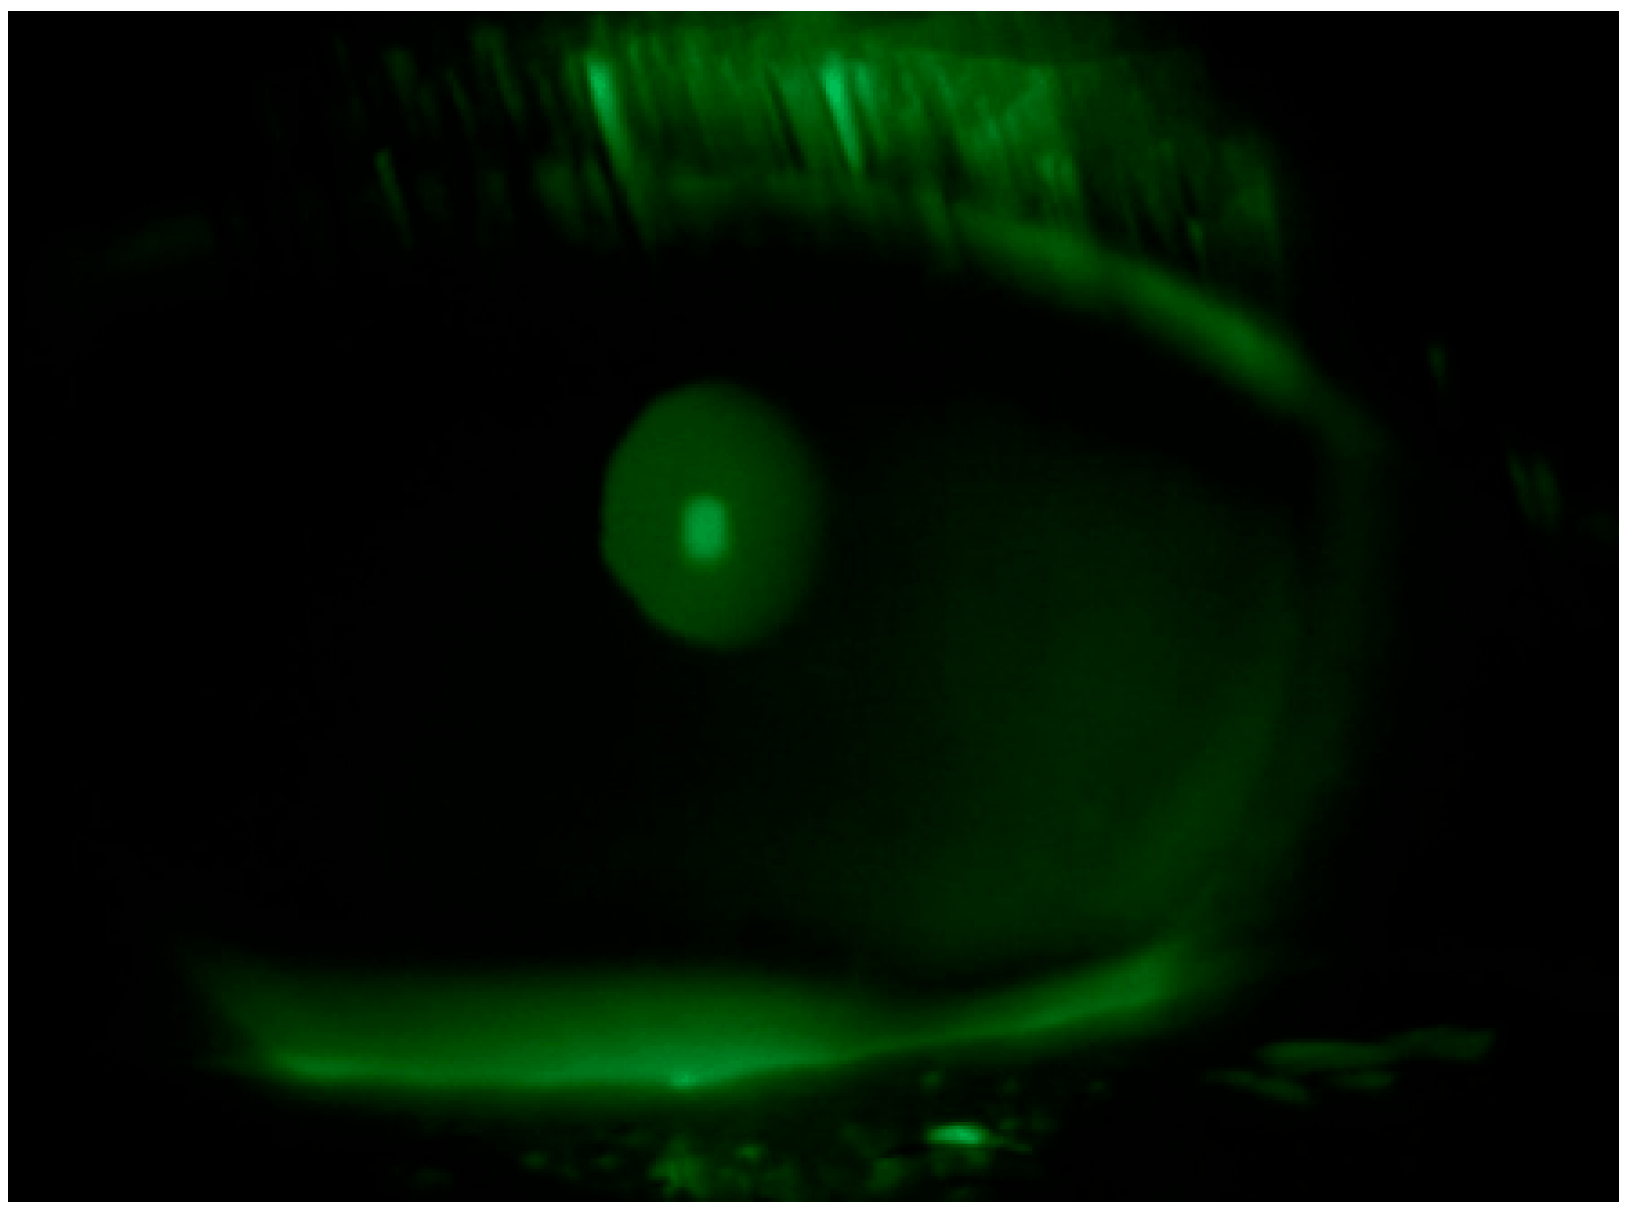

Tear substitute composed of hyaluronic acid, vitamin B2, vitamin E-TPGS, methylsulfonylmethane, and amino acids four times a day in both eyes and an antibiotic ointment (tetracycline + sulfamethylthiazole) before bedtime were prescribed; an ophthalmological follow up was performed after ten days: negative corneal Fluotest in both eyes (Figure 3 and Figure 4); TBUT right eye: 6 s, TBUT left eye: 5 s; Schirmer I test right eye: 10 mm, Schirmer I test left eye: 9 mm; and OSDI: 25.

Figure 3.

Fluotest on 10th day in the right eye.